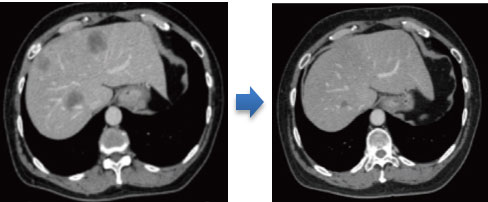

化学療法思考により、腫瘍縮小を認めた

腹腔鏡下大腸・肝臓同時切除術の施行や、切除不能と診断された肝転移症例の中から、化学療法後に切除可能となり手術を行った症例も存在します。遠隔転移のある大腸癌患者さんの治療について、いつでもご相談ください。